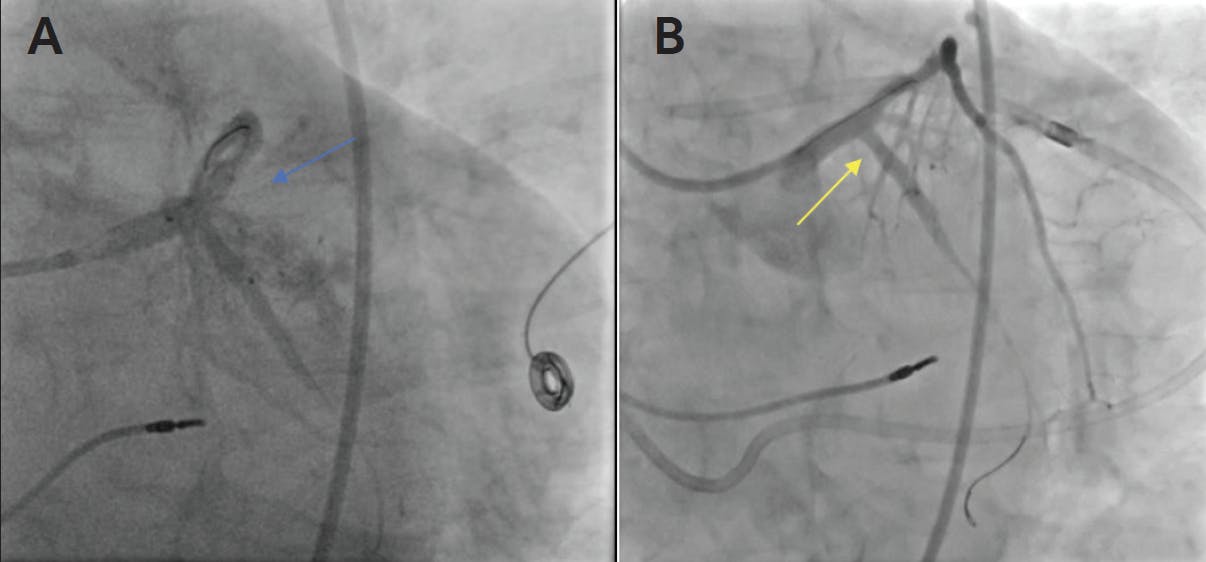

Originally designed for in-stent restenosis, covered stents now play a major role in CAP, especially in large-vessel perforations. Typically covered with polytetrafluoroethylene (PTFE), the main objective of a covered stent is to seal the perforation with a layer impermeable to blood. Deployment of a covered stent at the site of perforation can provide definitive treatment of large-vessel perforations, especially in vessels with a diameter > 2.5 mm (Figure 1). Since covered stents have been used to treat CAP, the need for emergency surgery has decreased and survival has increased. However, covered stents have some limitations. Covered stents should be used for perforations of vessels without sizable side branches as they carry the risk of side branch occlusion and periprocedural myocardial infarction. Also, thrombogenicity is of concern with covered stents, especially those covered with PTFE. Newer-generation covered stents contain graft material from autologous veins or equine pericardium to decrease thrombogenicity. Covered stents successfully provide hemostasis in approximately 85% of grade III coronary perforations.2,5

Figure 1. Ellis type III perforation of the proximal circumflex artery (A; blue arrow) successfully treated with 3- X 15-mm Papyrus covered stent (B; yellow arrow).